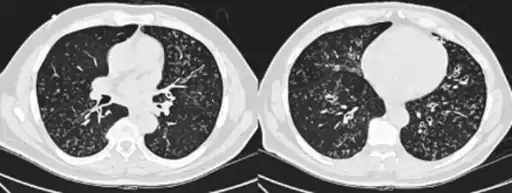

High-resolution computed tomography scan of the thorax

High resolution computed tomography (HRCT) images of the lower chest in a 16-year-old boy initially diagnosed with DPB (left), and 8 weeks later (right) after a 6-week course of treatment with erythromycin. The bilateral bronchiectasis and prominent centri-lobular nodules with a "tree-in-bud" pattern shows noticeable improvement.